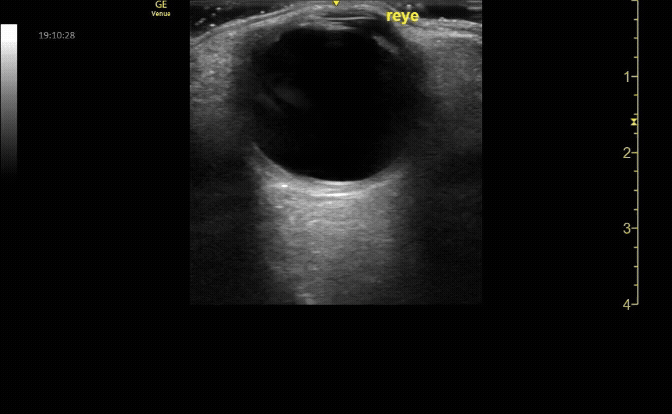

Measure the optic nerve sheath diameter (ONSD) 3mm from the back of the eye. The ONSD should measure <5mm across.

c/o John Elue, MD